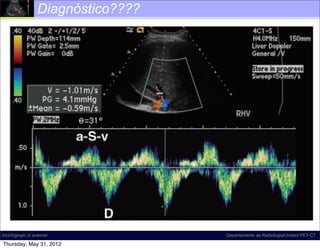

Diagnóstico????

Insuficiencia tricuspídea

moderada (S < D, >>> a/v)

Insuficiencia tricuspídea grave

moderada (S <onda S) a/v)

(inversión D, >>>